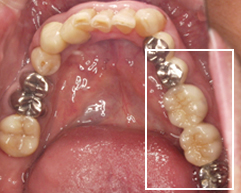

左上奥から2番目がインプラントを埋入しセラミックを入れた歯です。

十分な隙間を作ってからインプラントを行なったので、歯を削ることなく治療することができました。

治療前の下の歯

↓

治療後の下の歯

インプラント埋入後、セラミックと金属 を使用